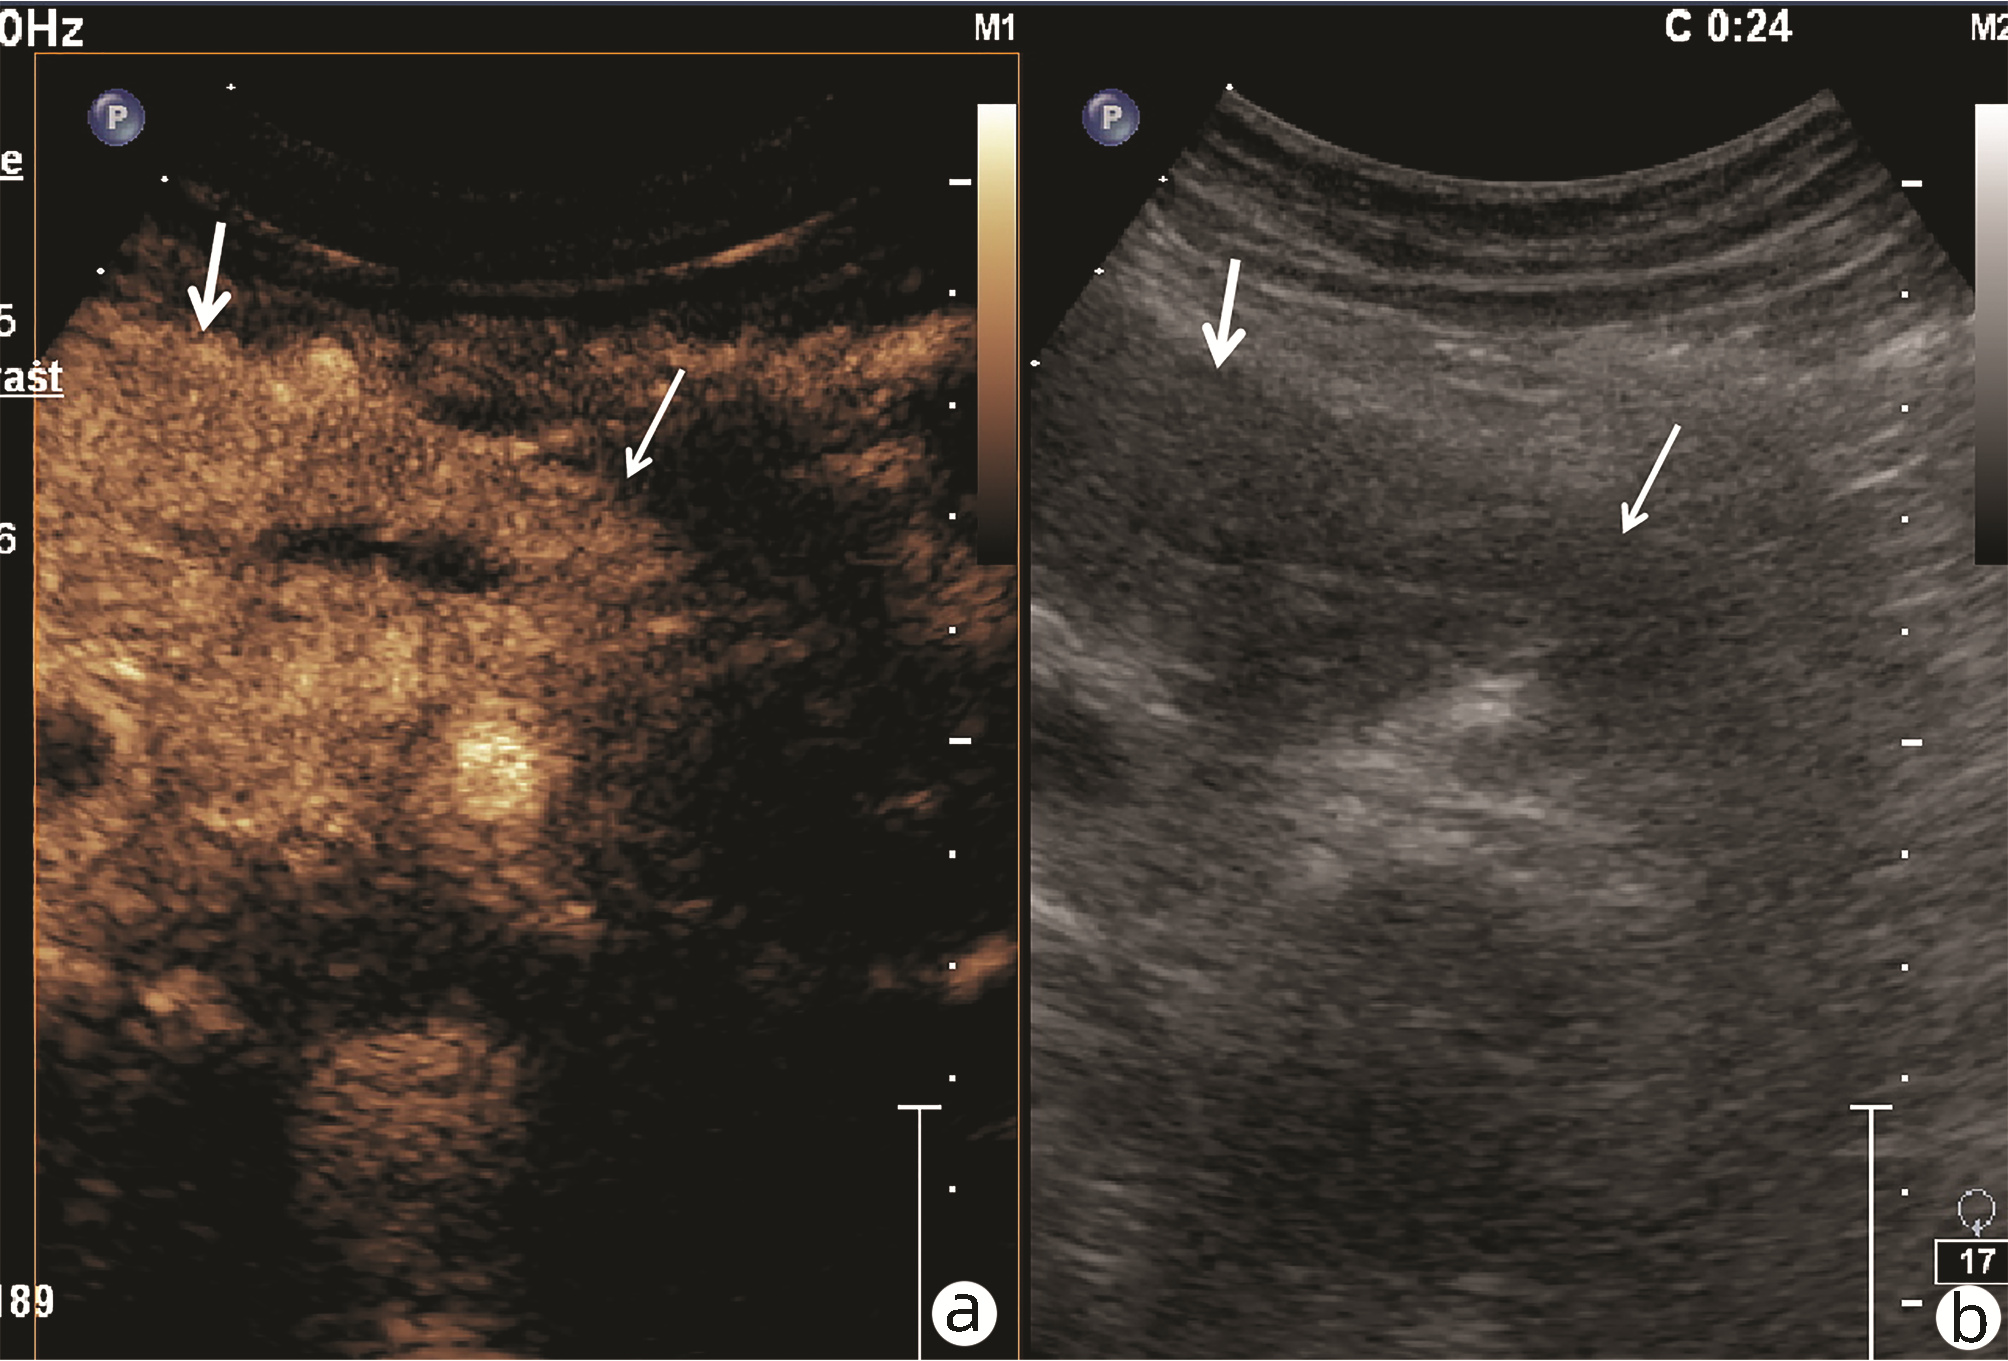

•   Objective  To investigate the value of ultrasound and contrast-enhanced ultrasound (CEUS) in the differential diagnosis of mass-type autoimmune pancreatitis (AIP) and pancreatic ductal adenocarcinoma (PDAC).  Methods  A retrospective analysis was performed for the clinical data, ultrasound findings, and CEUS findings of 11 patients with mass-type AIP who were diagnosed in Tangshan Workers' Hospital from January 2015 to December 2020, and their characteristic manifestations were analyzed and compared with the data of 23 patients with PDCA. The chi-square test was used for comparison of categorical data between two groups.  Results  For the 11 patients with mass-type AIP, CEUS had a diagnostic accuracy of 63.64%, and all of these patients had hypoechoic single lesions; the patients with clear boundaries, regular morphology, pancreatic duct dilatation or cutoff, and blood flow signal accounted for 54.55%, 63.64%, 18.18%, and 36.36%, respectively, while in the PDCA group, such patients accounted for 30.43%, 34.78%, 78.26%, and 21.74%, respectively, and there was a significant difference in the presence or absence of pancreatic duct dilatation or cutoff between the two groups(χ2=11.089, P < 0.05), with no significant differences in the other indices (all P > 0.05). For the 11 patients with mass-type AIP, CEUS showed that 7 patients (63.64%) had hyperenhancement and 4 (36.36%) had iso-enhancement in the arterial phase, and 5 patients (45.45%) had hyperenhancement in the arterial phase and 6 (54.55%) had iso-enhancement in the venous phase; for the 23 patients with PDCA, 22 (95.65%) had hypoenhancement of lesions in both arterial and venous phases, and there were significant differences in the enhancement pattern in arterial and venous phases between the two groups (χ2=30.345 and 30.084, both P < 0.05).  Conclusion  The enhancement pattern of CEUS and the presence or absence of pancreatic duct dilatation or cutoff have a relatively high value in the differential diagnosis of mass-type AIP and PDCA.